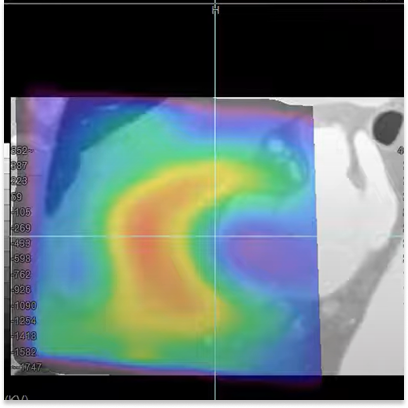

This protocol fuses functional (SPECT) and anatomic (CT) cardiac studies, supporting analysis of stress, rest and reversibility.